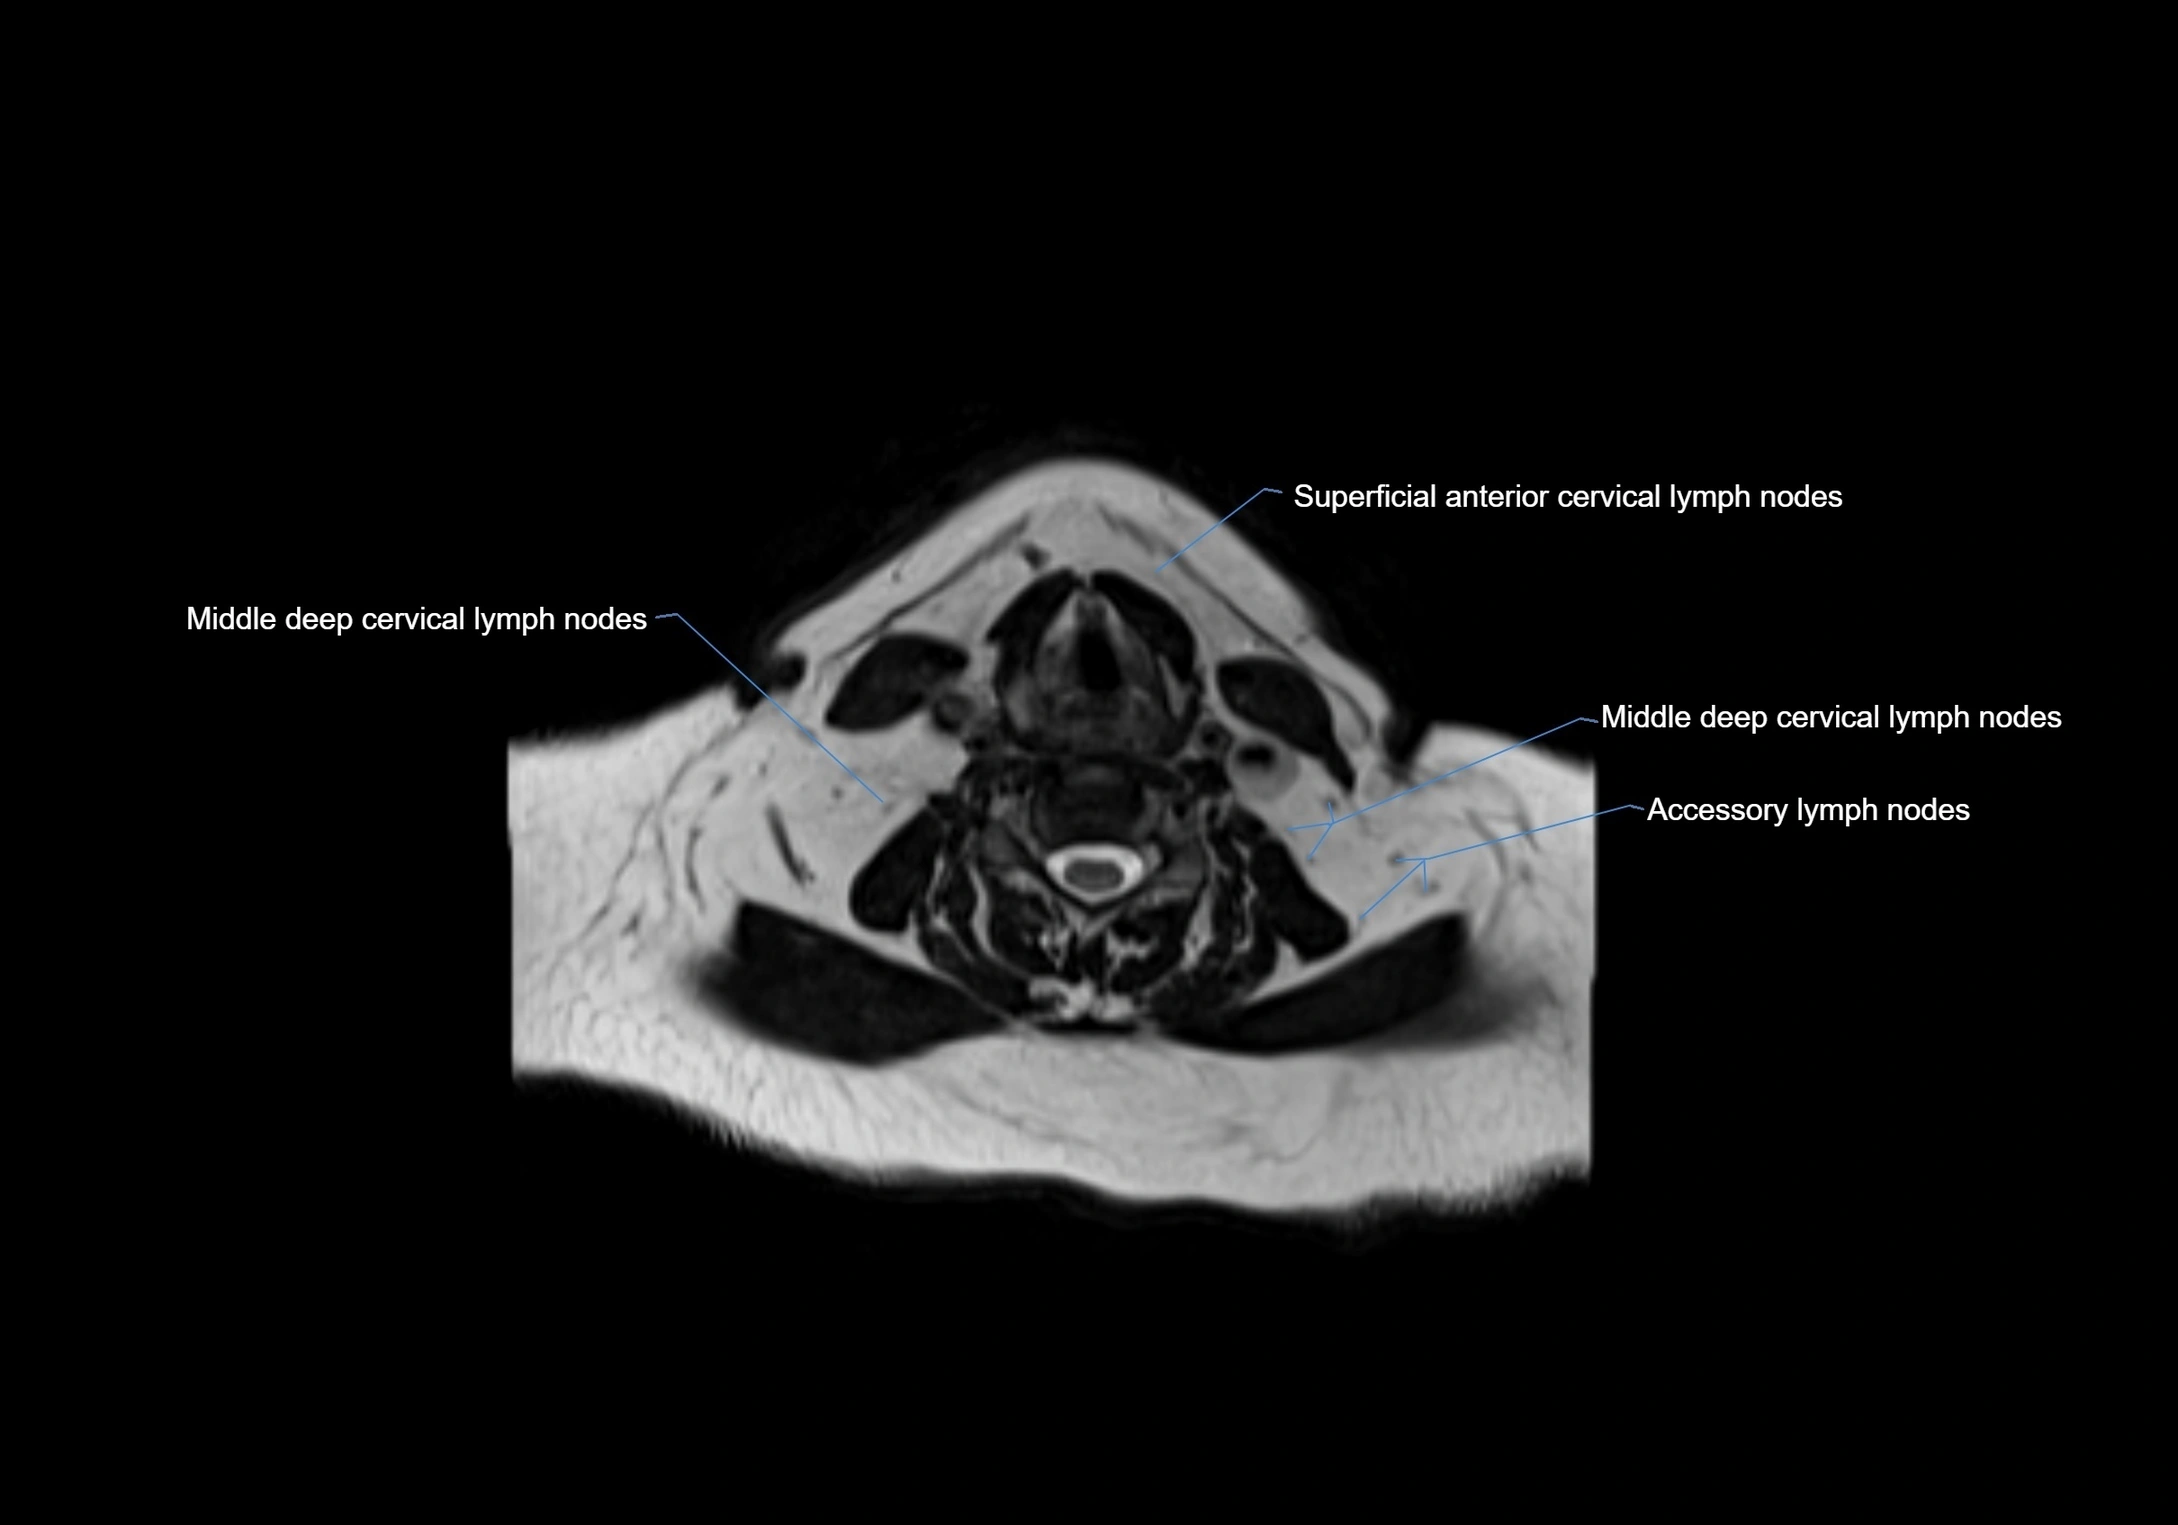

MRI Appearance

T1-weighted images:

• Normal accessory nodes appear as small, oval hypointense to intermediate signal structures within subcutaneous fat

• Surrounded by hyperintense fat, enhancing contrast for visualization

• Pathological nodes may appear enlarged or rounded, sometimes with cortical thickening

T2-weighted images:

• Nodes show intermediate signal, with surrounding fat bright

• Useful for detecting edema, inflammation, or infiltration

• Fatty hilum may appear slightly hyperintense relative to cortex

image